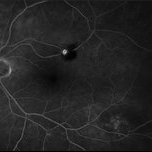

Retinal Microaneurysms & Dot/Blot Hemes Fundus Photo OS

May 12 2025 by Briana Hernandez

OS Optos Fundus Photo of Retinal Microaneurysms & Dot/Blot Hemes in 91-year-old female BRVO patient.

Photographer: Briana Hernandez, Hilton Head Retina Institute

Imaging device: Optos

Condition/keywords: macular